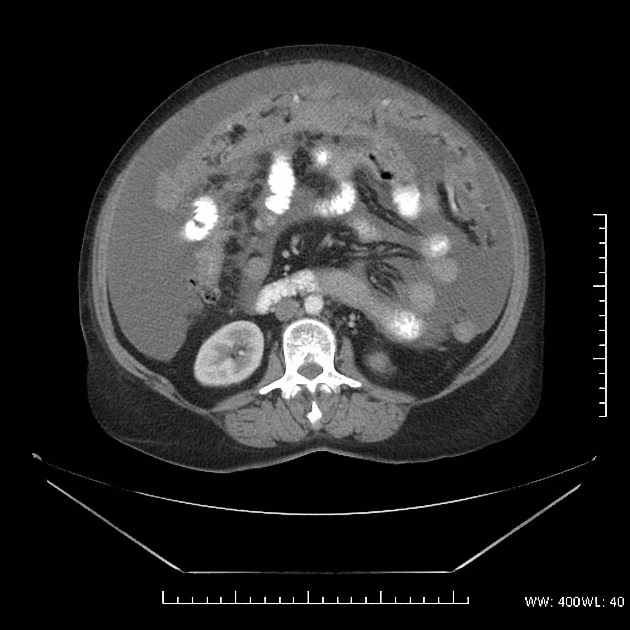

La torta omental no es una enfermedad en sí misma, sino un signo radiológico. Se define como un engrosamiento difuso e irregular de la grasa del epiplón. Normalmente, el epiplón es una banda de tejido graso delgada y casi imperceptible en las pruebas de imagen. Cuando se infiltra por células anormales (ya sean cancerosas, inflamatorias o infecciosas), se engrosa, se vuelve denso y adquiere una apariencia de 'masa' o 'torta' en estudios como la tomografía computarizada o la ecografía. Esta transformación es una señal de alerta que indica que algo anormal está ocurriendo en la cavidad abdominal.

- Tomografía Computarizada (TC): Es el gold standard. Permite ver con gran detalle el engrosamiento del epiplón, su patrón (difuso o nodular) y si hay afectación de otros órganos.